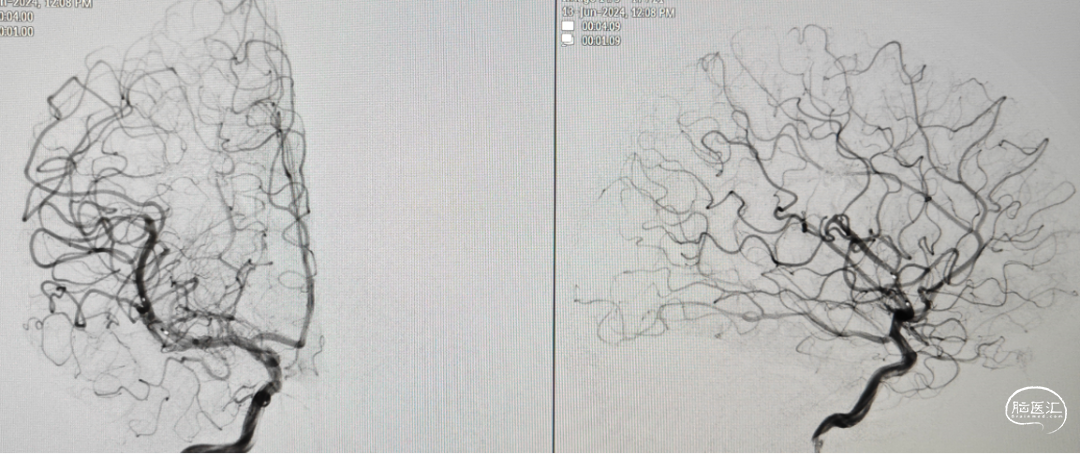

10个月DSA复查

术后4个月复查DSA血管畸形无复发